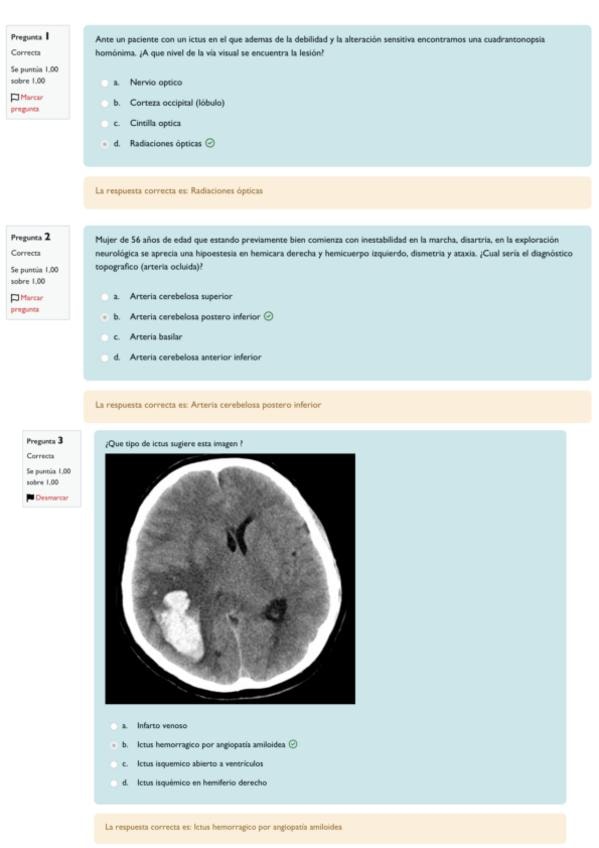

He publicado nuevos examenes de 4º Patología del Sistema Nervioso y Geriatría: Ordinaria-junio-2025.pdf

He publicado nuevos examenes de 4º Patología del Sistema Nervioso y Geriatría: Ordinaria-2025-Respuestas.pdf